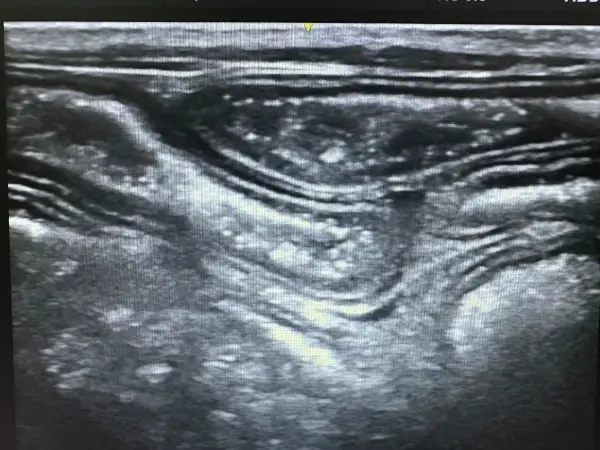

Ecografía abdominal y cardíaca: La ecografía es una técnica no invasiva que permite visualizar órganos internos en tiempo real, evaluando su estructura, tamaño y vascularización. A diferencia de la radiografía, no utiliza radiación y proporciona información sobre la arquitectura interna de los órganos.

Nuestro ecógrafo de alta gama con tecnología doppler color permite:

- Evaluación detallada de riñones, hígado, bazo, páncreas e intestino

- Diagnóstico de masas abdominales y diferenciación de su naturaleza

La ecografía abdominal es especialmente útil en el diagnóstico de enfermedad renal crónica, permitiendo evaluar el tamaño, la ecogenicidad y la arquitectura renal. Podemos detectar quistes, cálculos renales, hidronefrosis y cambios estructurales indicativos de daño renal antes de que aparezcan síntomas clínicos.